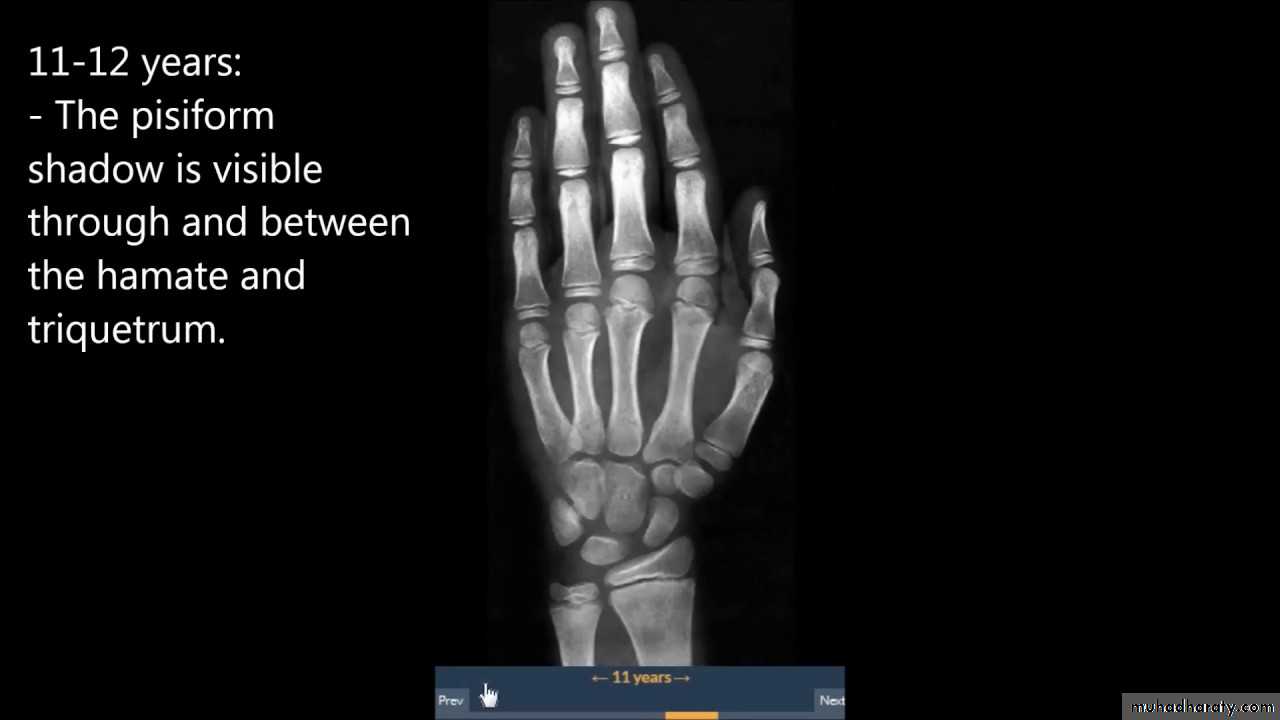

• عمليا يتم تصوير الرسغ والمرفق والكتف لمن يبدوا ظاهرا دون سن العشرين عاما من العمر. ويصور الحرقف لمن بدا في اواسط العقد الثالث من العمر او اقل, والنهاية الانسية للترقوة والتحام القص بالرهابة لمن تجاوز ذلك.

55• معدل ظهور والتحام المراكز التعظمية تبعا للعمر:

• 4) وفي بداية السنة الخامسة يظهر متع للعظم المربع المنحرف وفي نهاية السنة االخامسة يظهر المركز التعظمي لعظمي شبه المنحرف والزورقي الرسغيين.

7) في نهاية السنة التاسعة يظهر متع للنتوء المرفقي لعظم الزند والعظم الحمصي.